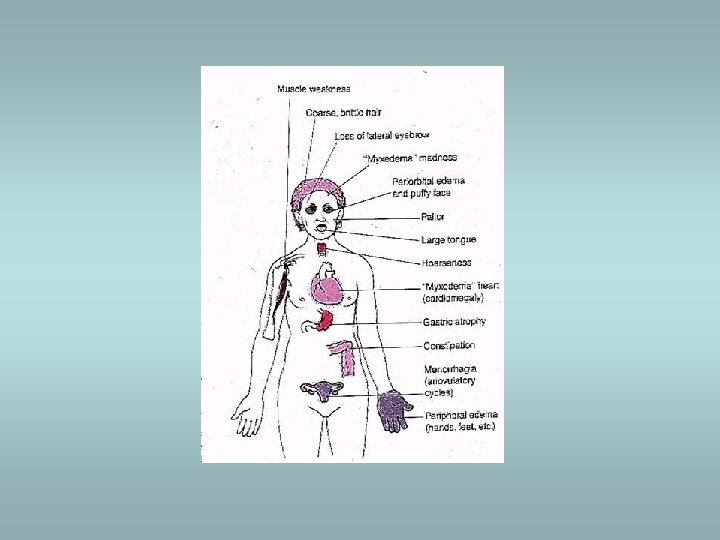

Hypothyroidism Cretinism (during infancy) ü Endemic form ü Sporadic form ü Physical an mental retardation Myxoedema (in adults) Slowing of physical and mental activity, fatigue and apathy Signs - periorbital oedema, coarsening of skin, cardiomegaly, accumulation of mucopolysaccharides in dermis Various causes - idiopathic primary, inflammation – Hashimoto thyroiditis, etc.